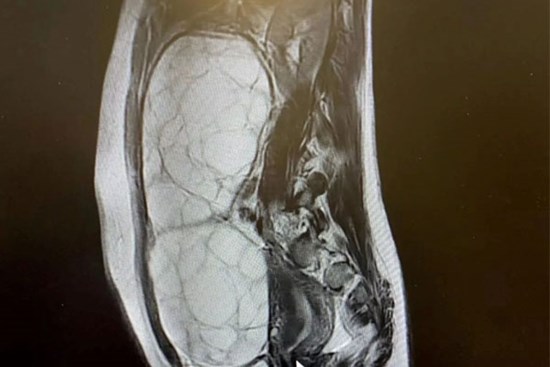

Mang khối u nặng 10kg nhưng tưởng béo bụng

Bà P. thấy bụng to bất thường, cứng nên được người nhà khuyên đi khám. Kết quả, bệnh nhân có khối u xơ nặng 10kg.